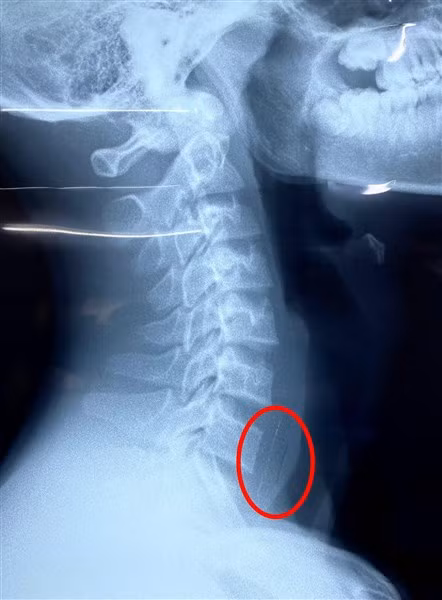

Dị vật nằm dưới miệng thực quản 2cm. Ảnh: BVCC.

Sau nuốt, bé đau họng nhiều, không ăn uống được, không khó thở. Kết quả chụp Xquang ghi nhận hình ảnh nghi ngờ dị vật cản quang vùng thực quản.

Ngay lập tức, bệnh nhi được chuyển đến Khoa Tai Mũi Họng của Bệnh viện Nhi đồng 1 để thực hiện nội soi cấp cứu gắp dị vật. “Do vỏ viên thuốc to và sắc nhọn, nằm bên dưới miệng thực quản khoảng 2cm, nên các thao tác thực hiện thủ thuật cần phải thật khéo để tránh làm tổn thương thêm niêm mạc thực quản”, BS.CKI Lý Phạm Hoàng Vinh chia sẻ.